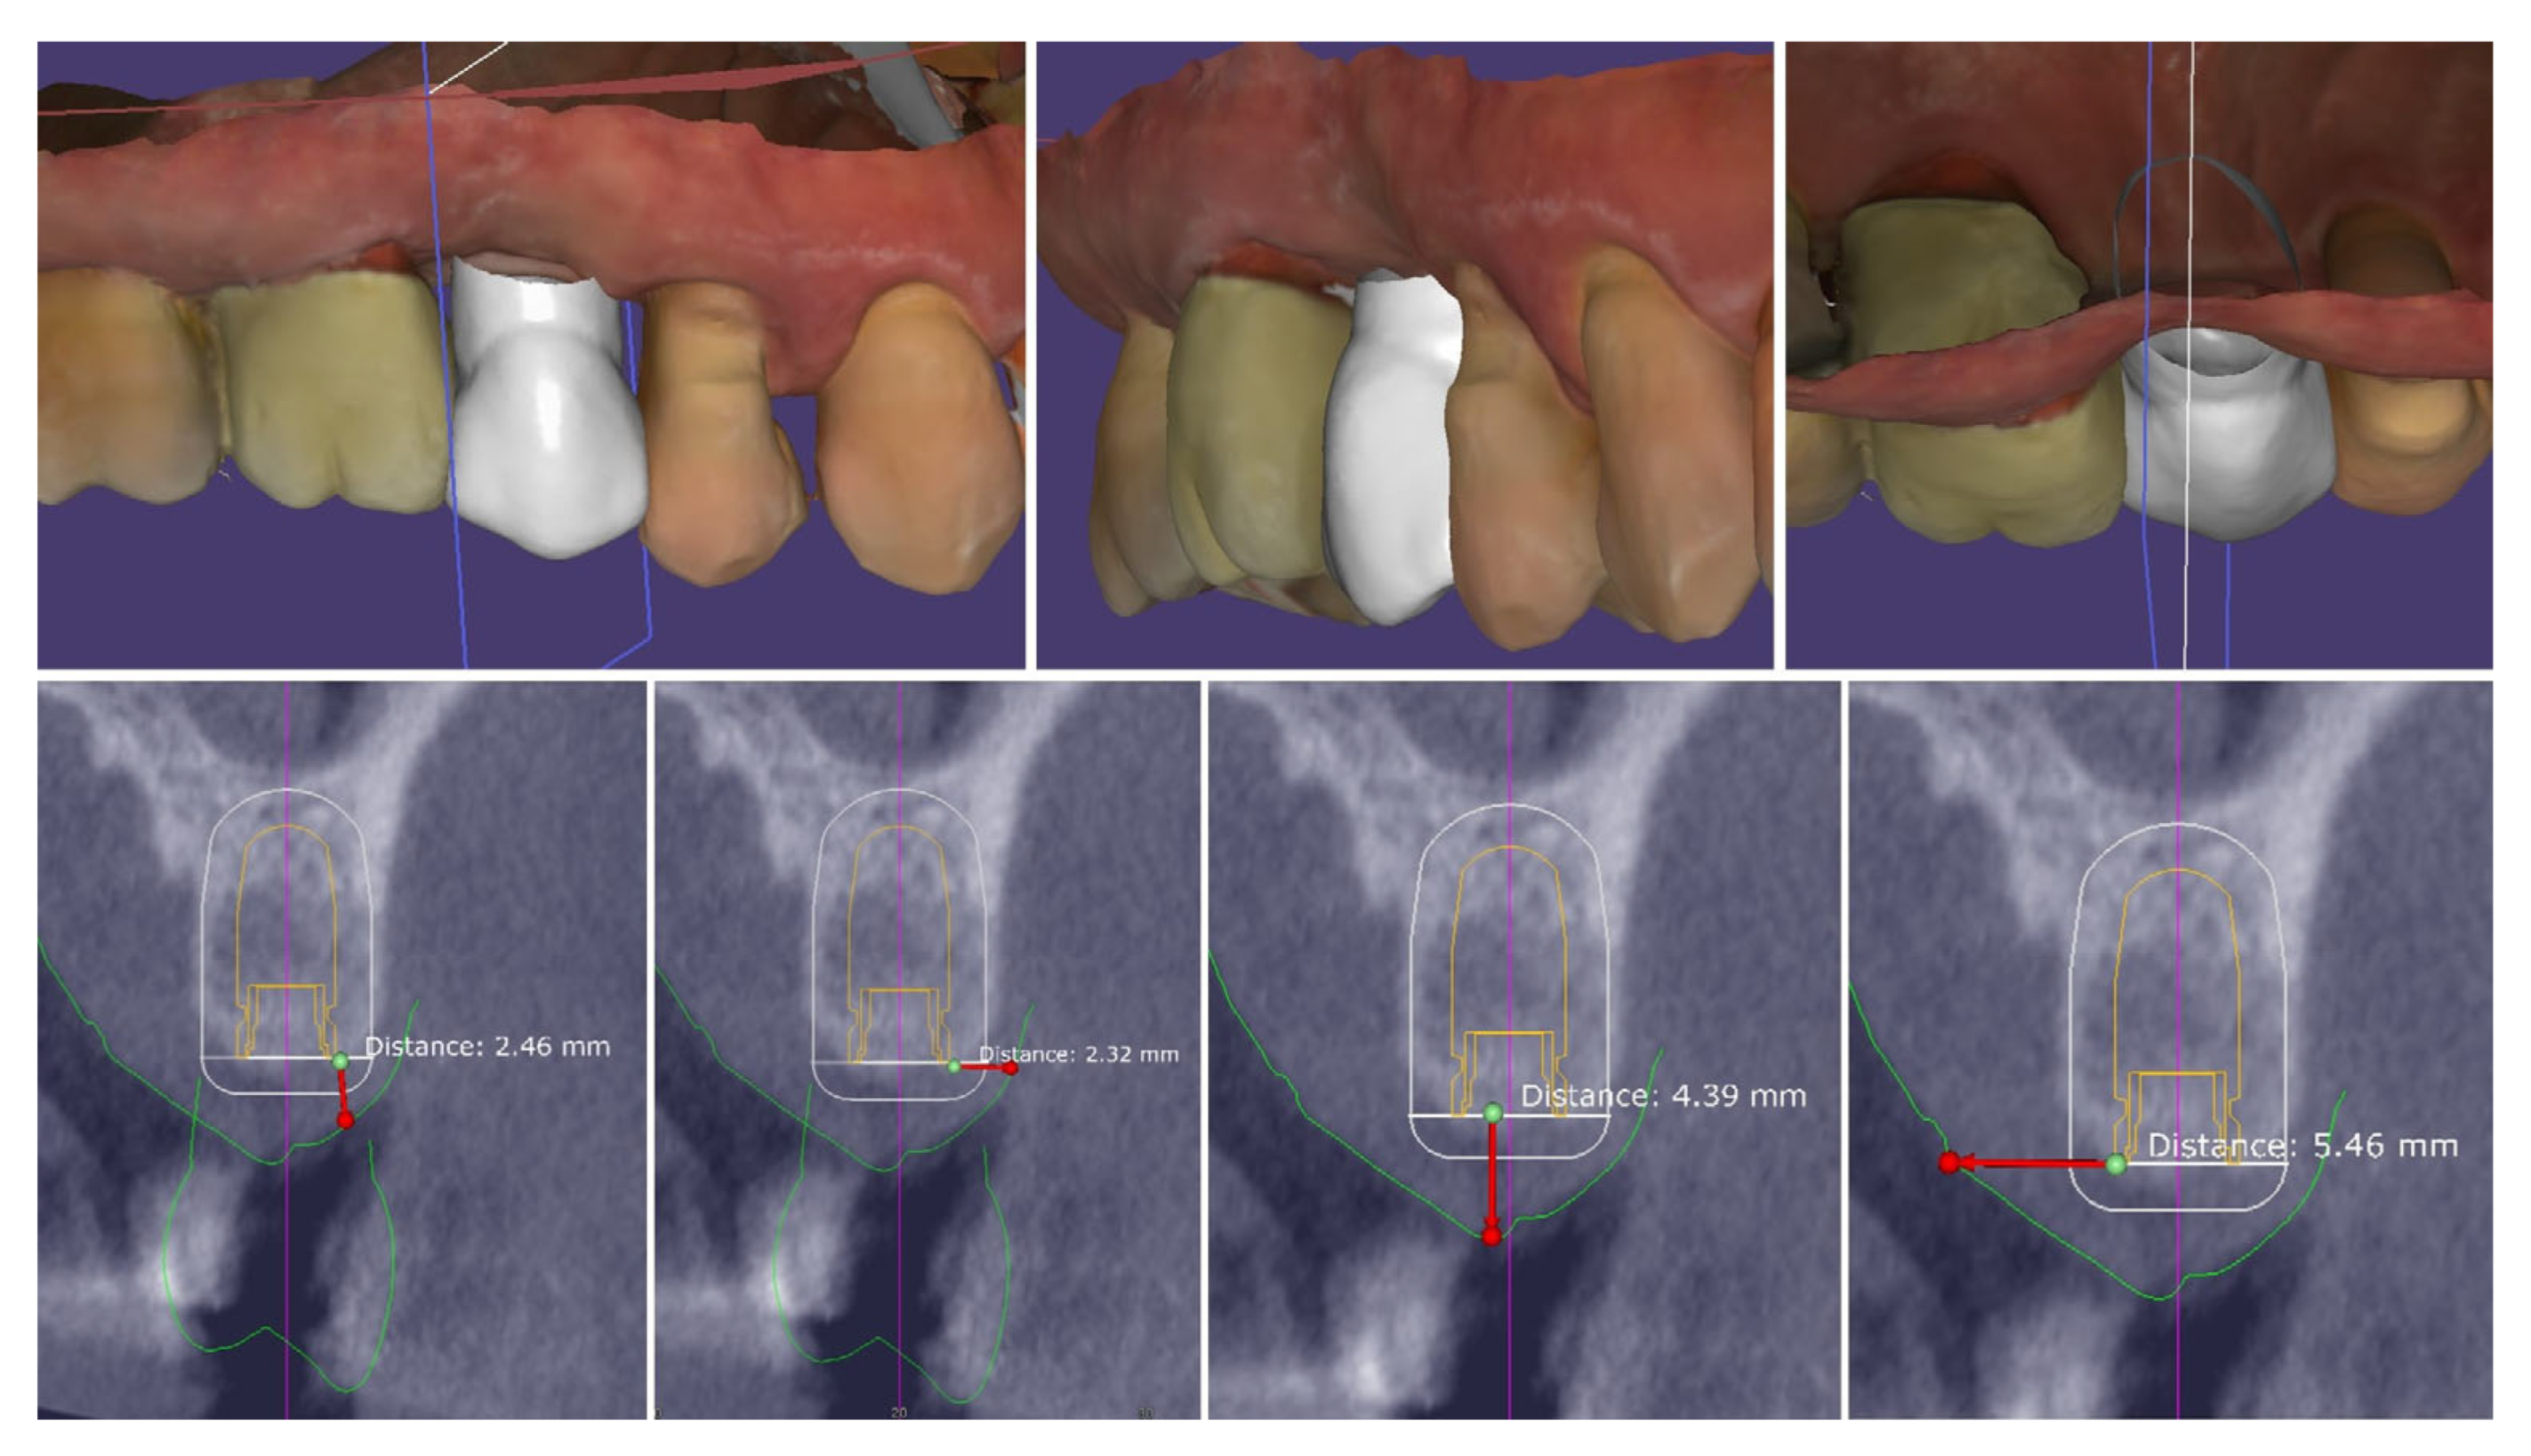

| Timepoint | Horizontal Thickness (mm) | Vertical Thickness (mm) | Clinical/Radiographic Findings | |

|---|---|---|---|---|

| 1 | Baseline (Day 0) | 2.3 | 2.4 | Initial thin buccal tissue |

| 2 | 2 weeks post-op | Uneventful healing, stable mucosal margin | ||

| 3 | 3 months post-op (with provisional) | 3.4 | 3.4 | Increased thickness, stable bone and mucosa |

| 4 | 4 months post-provisional | 3.5 | 3.6 | Stable peri-implant mucosa around provisional crown |

| 5 | 8 months post-op (final crown) | 3.5 | 4.1 | Final crown placed, harmonious soft tissue contours, and stable crestal bone |

| 6 | 14 months post-definitive | Long-term stability of soft tissue and crestal bone confirmed |